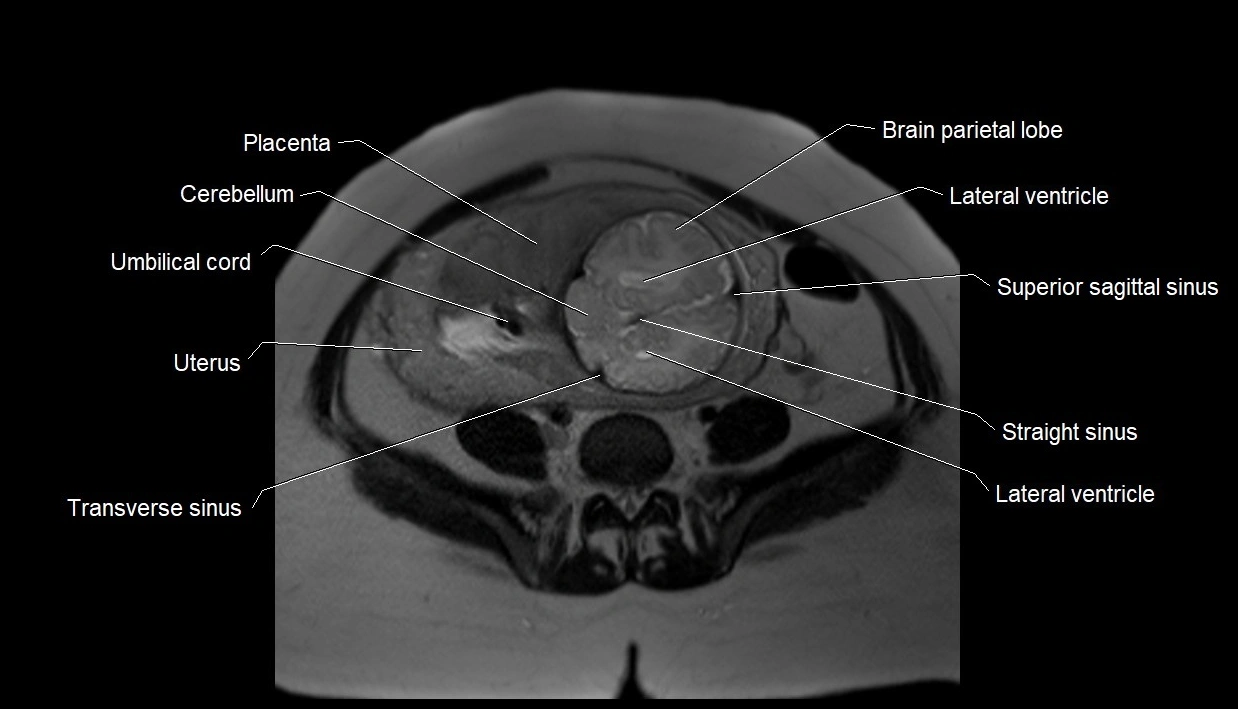

MRI Appearance

T2 HASTE (T2 GRE):

• Amniotic fluid shows very bright hyperintense signal

• Provides natural contrast against fetus and placenta

• Small particles (vernix) may appear as scattered hypointense foci within bright fluid